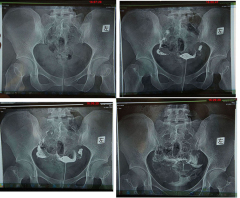

输卵管造影是通过导管向宫腔及输卵管注入造影剂,利用X线诊断仪行X线透视及摄片,根据造影剂在输卵管及盆腔内的显影情况来了解输卵管是否通畅。>>点击了解详情

(一)器械要求--500ma高精度X光机:

相比较于其它医院300ma的X光机,杭州红房子500ma高精度X光机有效度,专业医生熟练操作并并附以数字X光机的应用,医生可以观察到相关局部的情况,显示所有的软组织及活动情况,诊断相关的内部功能,清晰准。>>>输卵管造影检查疼吗?